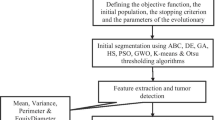

The performance of medical image segmentation is generally affected by the parameters of the adopted method and noise. To overcome these issues we introduce in this paper a novel segmentation approach of brain MRI using a region based-active contour model and evolutionary algorithm and without performing any pre-processing step. Our main objective is to accurately extract edges, resolve the intensity inhomogeneity problem and overcome manifestations of noise. Chan and Vese model was adopted by introducing a local similarity factor based on Bilateral filter principle (LSFB). The adjustment of our functional energy parameters was achieved using a multi-population genetic algorithm (MPGA) which can display better search performance than serial single population models, in terms of the quality of the solution found, effort and processing time. We selected Brain MRI from Oasis and Brainweb data base with different noise type. The initialization of the active contour was totally random. A comparison of segmentation results with Chan and Vese model and active contour model with a locally computed signed pressure force (SPF) of Akram and his team reveals a clear efficiency of our proposed approach.

F. Z. Belgrana, N. Benamrane, and A. Taleb-Ahmed, “Adjustment of active contour parameters in brain MRI segmentation using evolution strategies,” in 4th International Conference on Electrical Engineering (ICEE) (2015), pp. 1–7.

F. Z. Belgrana and N. Benamrane, “A fast and robust segmentation of magnetic resonance brain images using a combination of the pyramidal approach and level set method,” Int. J. Imaging Syst. Technol. 27 (2), 182–182 (2016).